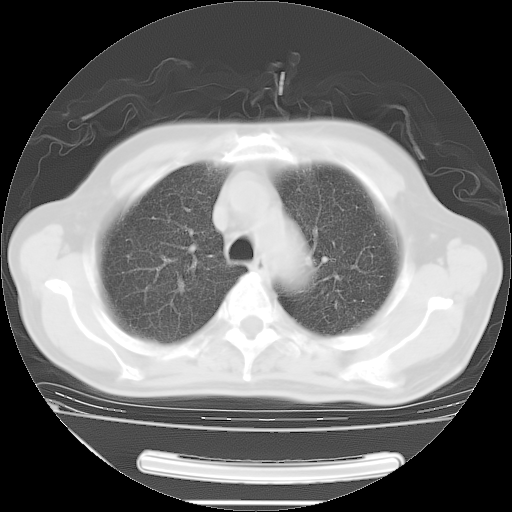

今天复查肺部CT,发现双肺广泛磨玻璃样改变。所以我把3月19日和5月9日相隔50天的肺部CT上传。请大家会诊。

2009年3月19日肺部CT片。

2009年3月19日肺部CT

大致读了系列胸部CT:纵隔窗无明显异常,肺窗:从4、27至今:主要是双肺中下野外带可见毛玻璃样改变,目前处于急性肺泡炎阶段,至于原因考虑1、结替组织或胶原血管性疾病所致?2、恶性疾病如恶组在肺部所致的表现或细支气管肺泡癌?3、药物或其它原因如肺蛋白沉着症所致肺泡炎目前不太可能?总之,明天就去请我院的呼吸科、感染科、血液科和临免专家会诊哈。